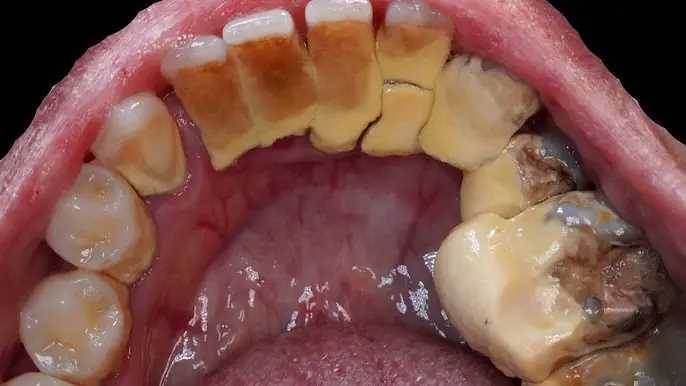

A 28-year-old woman undergoes a full dental procedure combining scaling to remove heavy tartar buildup and a tooth extraction for a damaged tooth. See the detailed process, tools used, and the dentist’s careful techniques from start to finish. Let’s watch the treatment in action…